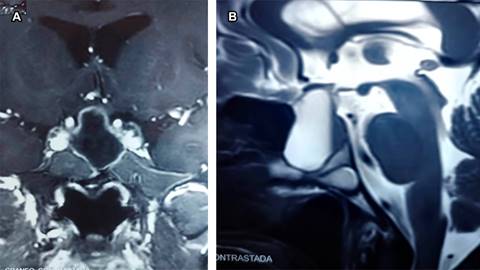

Se efectuó cirugía por vía transesfenoidal con resección total de la lesión y el reporte histopatológico confirmó QBR (Figura 2). El seguimiento cada seis meses con RM de control reportó silla turca vacía con cambios quirúrgicos; el último control con RM cinco años después de la cirugía mostró crecimiento tumoral (Figura 3). Fue reintervenido vía transesfenoidal con resección total del quiste y de la hendidura de Rathke; histopatológicamente se confirmó diagnóstico por fragmento de adenohipófisis con arquitectura histológica preservada y pared fibrosa de quiste. El control con RM después de seis meses no muestra progresión o crecimiento, el paciente se encuentra asintomático.

Figura 3: Imágenes de resonancia magnética cerebral con medio de contraste; en (A) ponderada en T1 en corte coronal y en (B) corte sagital ponderado en T2, se muestra proceso ocupativo intrasillar, con intensidad de líquido cefalorraquídeo de comportamiento hiperintenso, que corresponde a quiste de la bolsa de Rathke que incrementó su tamaño cinco años después de la primera cirugía.